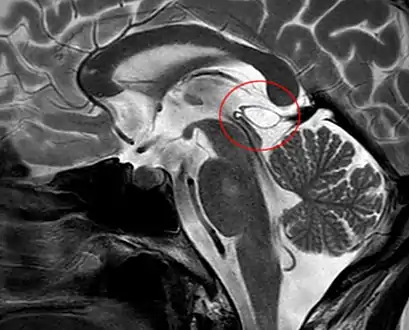

The National Organization for Rare Disorders states that pineal cysts larger than 5.0 mm are "rare findings" and are possibly symptomatic. If narrowing of the cerebral aqueduct occurs, many neurological symptoms may exist, including headaches, vertigo, nausea, muscle fasciculations, eye sensitivity, and ataxia. Continued monitoring of the cyst might be recommended to monitor its growth, and surgery may be necessary.[3]